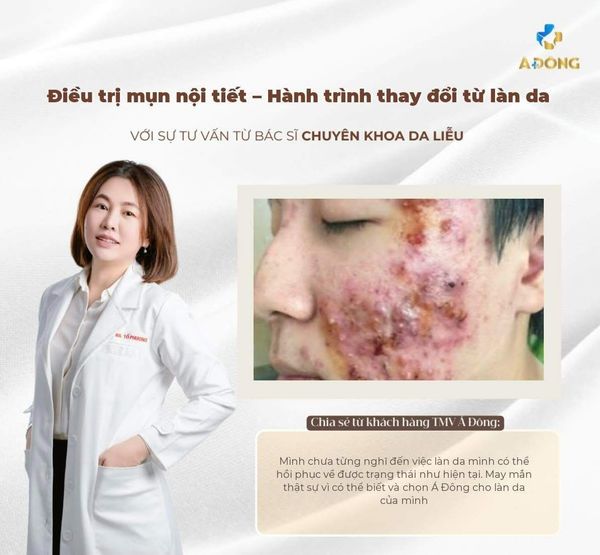

Mụn nội tiết không chỉ là mụn, mà còn là nỗi lo kéo dài khiến nhiều người mất tự tin.

Tại Thẩm Mỹ Á Đông, mỗi làn da được bác sĩ da liễu trực tiếp tư vấn và theo sát, xây dựng phác đồ phù hợp với từng tình trạng da.

![]() “Mình chưa từng nghĩ làn da có thể hồi phục được như hiện tại. Thật sự may mắn khi chọn Á Đông.”

“Mình chưa từng nghĩ làn da có thể hồi phục được như hiện tại. Thật sự may mắn khi chọn Á Đông.”

Á Đông không chỉ điều trị mụn, mà còn đồng hành cùng bạn trên hành trình phục hồi làn da khỏe đẹp từ bên trong ![]()